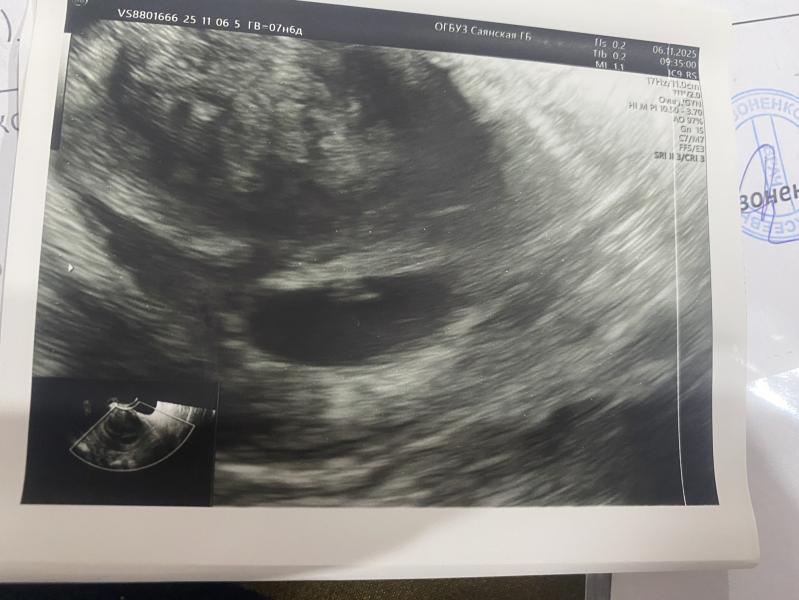

КТР 3.8 мм на 6 неделе беременности - норма или нет?

Вчера сходила на УЗИ

Беременность подтвердили

По месячным 7н6д

По УЗИ 6н

КТР 3.8 мм

ЧСС 118 уд/мин

Интересует КТР, посмотрела у других девочек на таком сроке, у них КТР намного больше, почему у меня так🤔

Узистка сказала, что все в норме